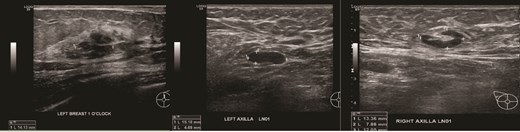

(Left, middle) Ultrasound images of the right breast irregular spiculated hypoechoic mass with ill-defined margins, associated with a dilated duct 3 mm; (Right) Ultrasound image of the enlarged axillary lymph node.

(Left) Ultrasound images of the left breast ill-defined hypoechoic mass; (Middle, Right) Ultrasound images of the axillary lymph nodes with cortical thickening and effacement of the fatty hilum.